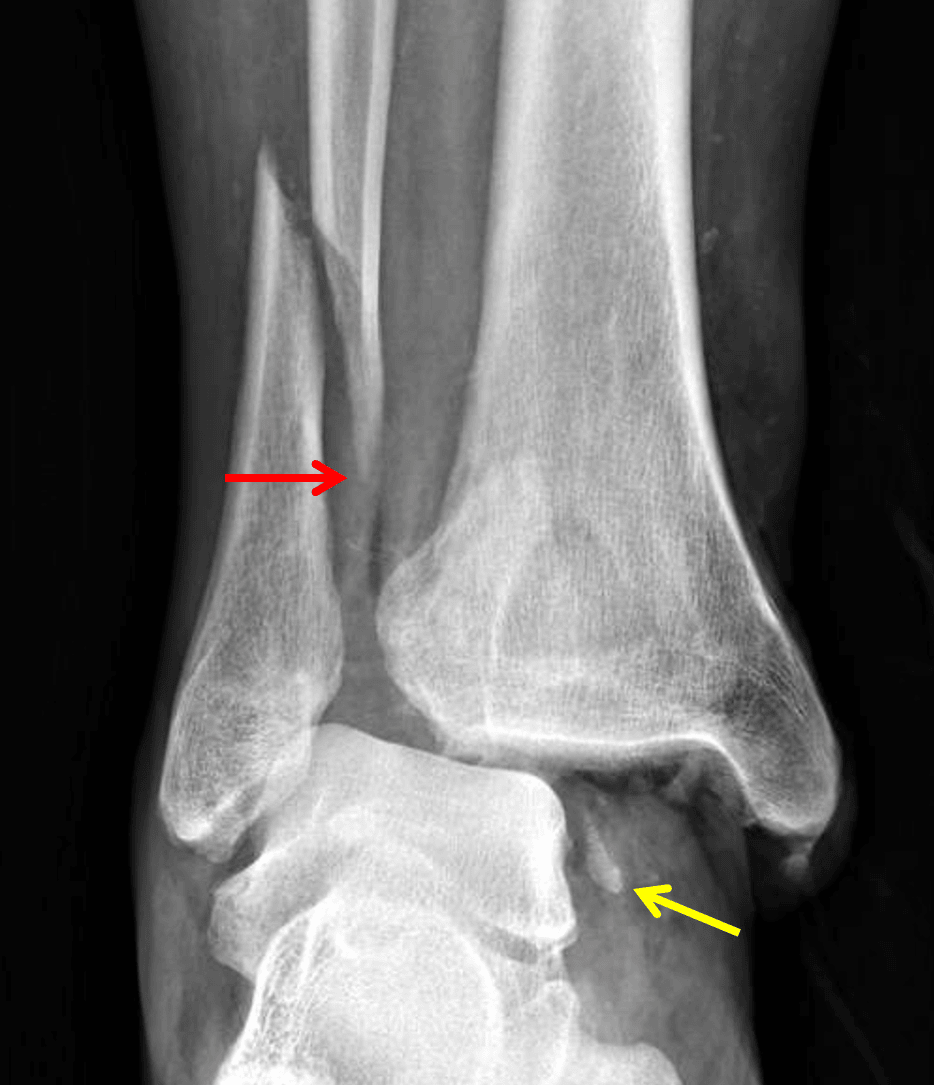

Weber type C fibular fracture (red arrow). Medial malleolar avulsion fracture remains associated with the talus (yellow arrow).

Acute oblique distal fibular fracture with one-half shaft width lateral displacement and inferomedial extension above the level of the distal tibiofibular syndesmosis.

Acute medial malleolar avulsion fracture, which maintains its relationship with the talus.

Approximately 50% lateral subluxation at the tibiotalar joint with medial clear space widening measuring 2.3 cm, concerning for injuries to the distal tibiofibular syndesmosis and deltoid ligament.